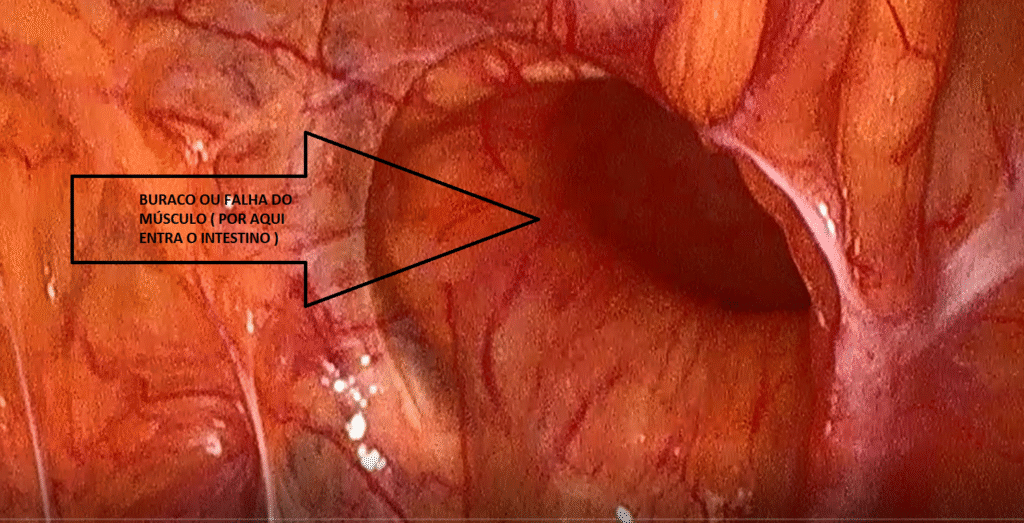

A hérnia inguinal acontece quando parte do intestino ou da gordura abdominal “escapa” por uma fraqueza natural ou adquirida ( uma espécie de “buraco” como visto na figura abaixo) na musculatura da região da virilha.

Buraco ou falha do músculo da virilha por dentro onde o intestino vai passar e gerar dor